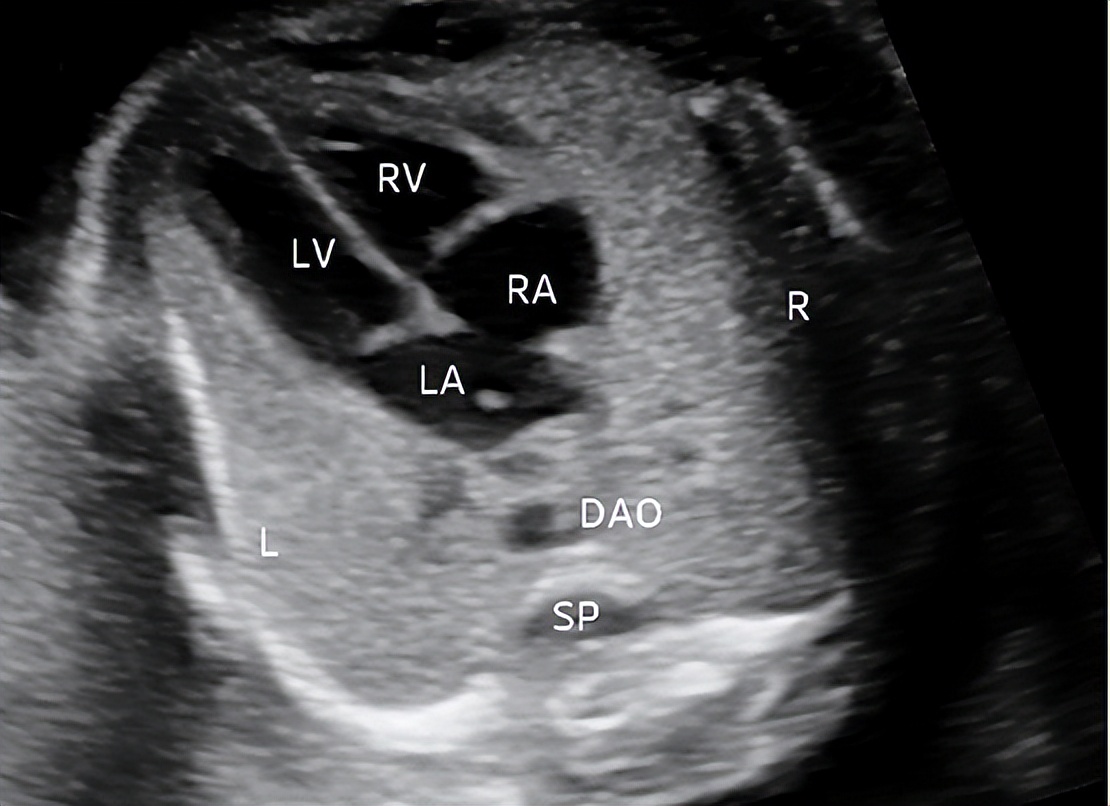

1.四腔心切面

切面要求:显示左右房室腔及两组房室瓣,同时至少显示一条完整肋骨(图1)。

观察内容:大部分心脏位于左侧胸腔,心尖指向左前方,心轴及心胸比正常,房室腔形态及比例正常,房室连接正常,彩色多普勒显示至少一条肺静脉汇入左心房,二尖瓣、三尖瓣启闭自如,左右两侧肺脏呈均匀回声。

图1 孕23周四腔心切面 显示左右房室腔及两组房室瓣(LA:左房;LV:左室;RA:右房;RV:右室;DAO:降主动脉;SP:脊柱;L:左侧;R:右侧)